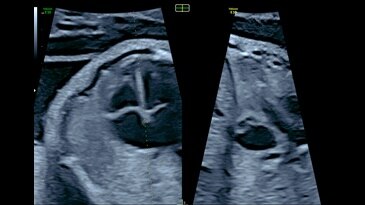

View of intraventricular septum with e4D Bi-plane imaging